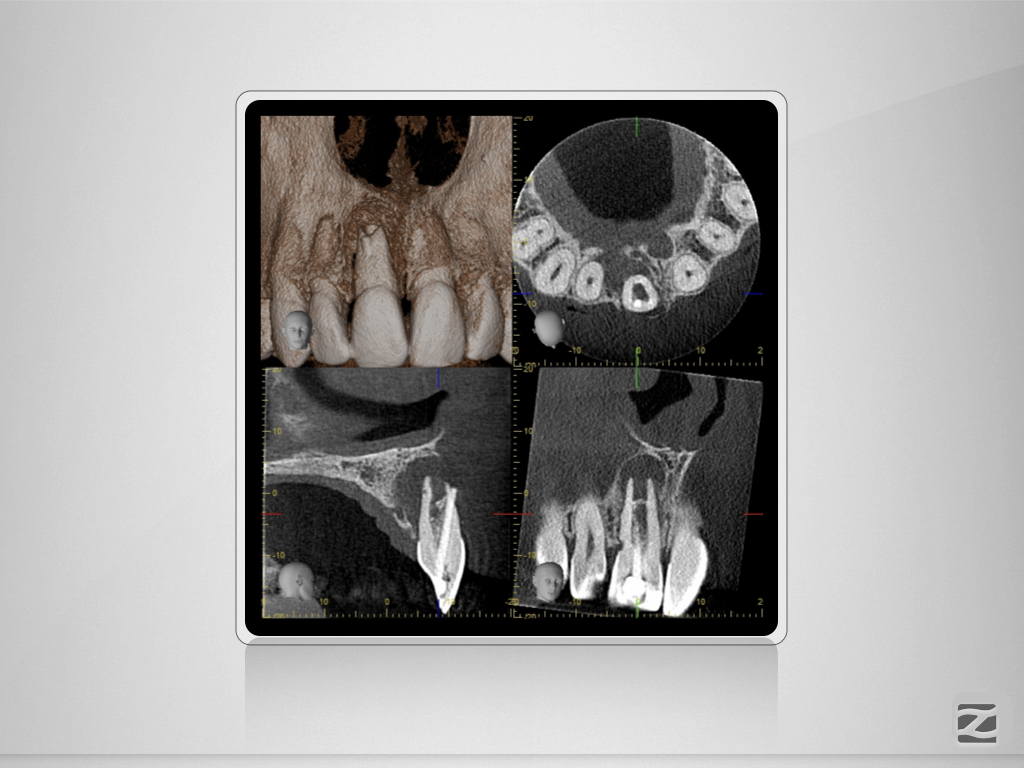

Traumabehandlung – State of the Unart